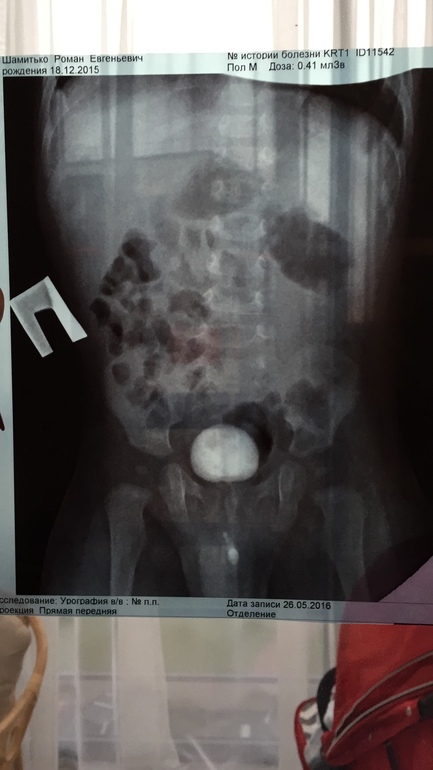

Мультикистоз почки

Да, почка "немая" там нет функции

Вероятно облитерация сосудов не полная и они поддерживают почку